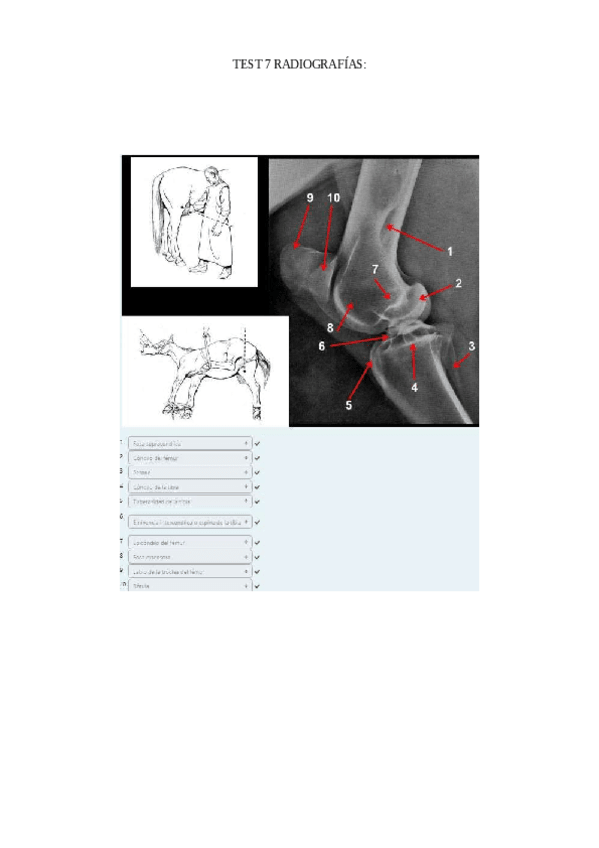

TEST-7-radiografias-corregido.pdf

Apuntes - Todas-las-radiografias.pdf

Apuntes - Todas-mis-radiografias-resueltas.pdf